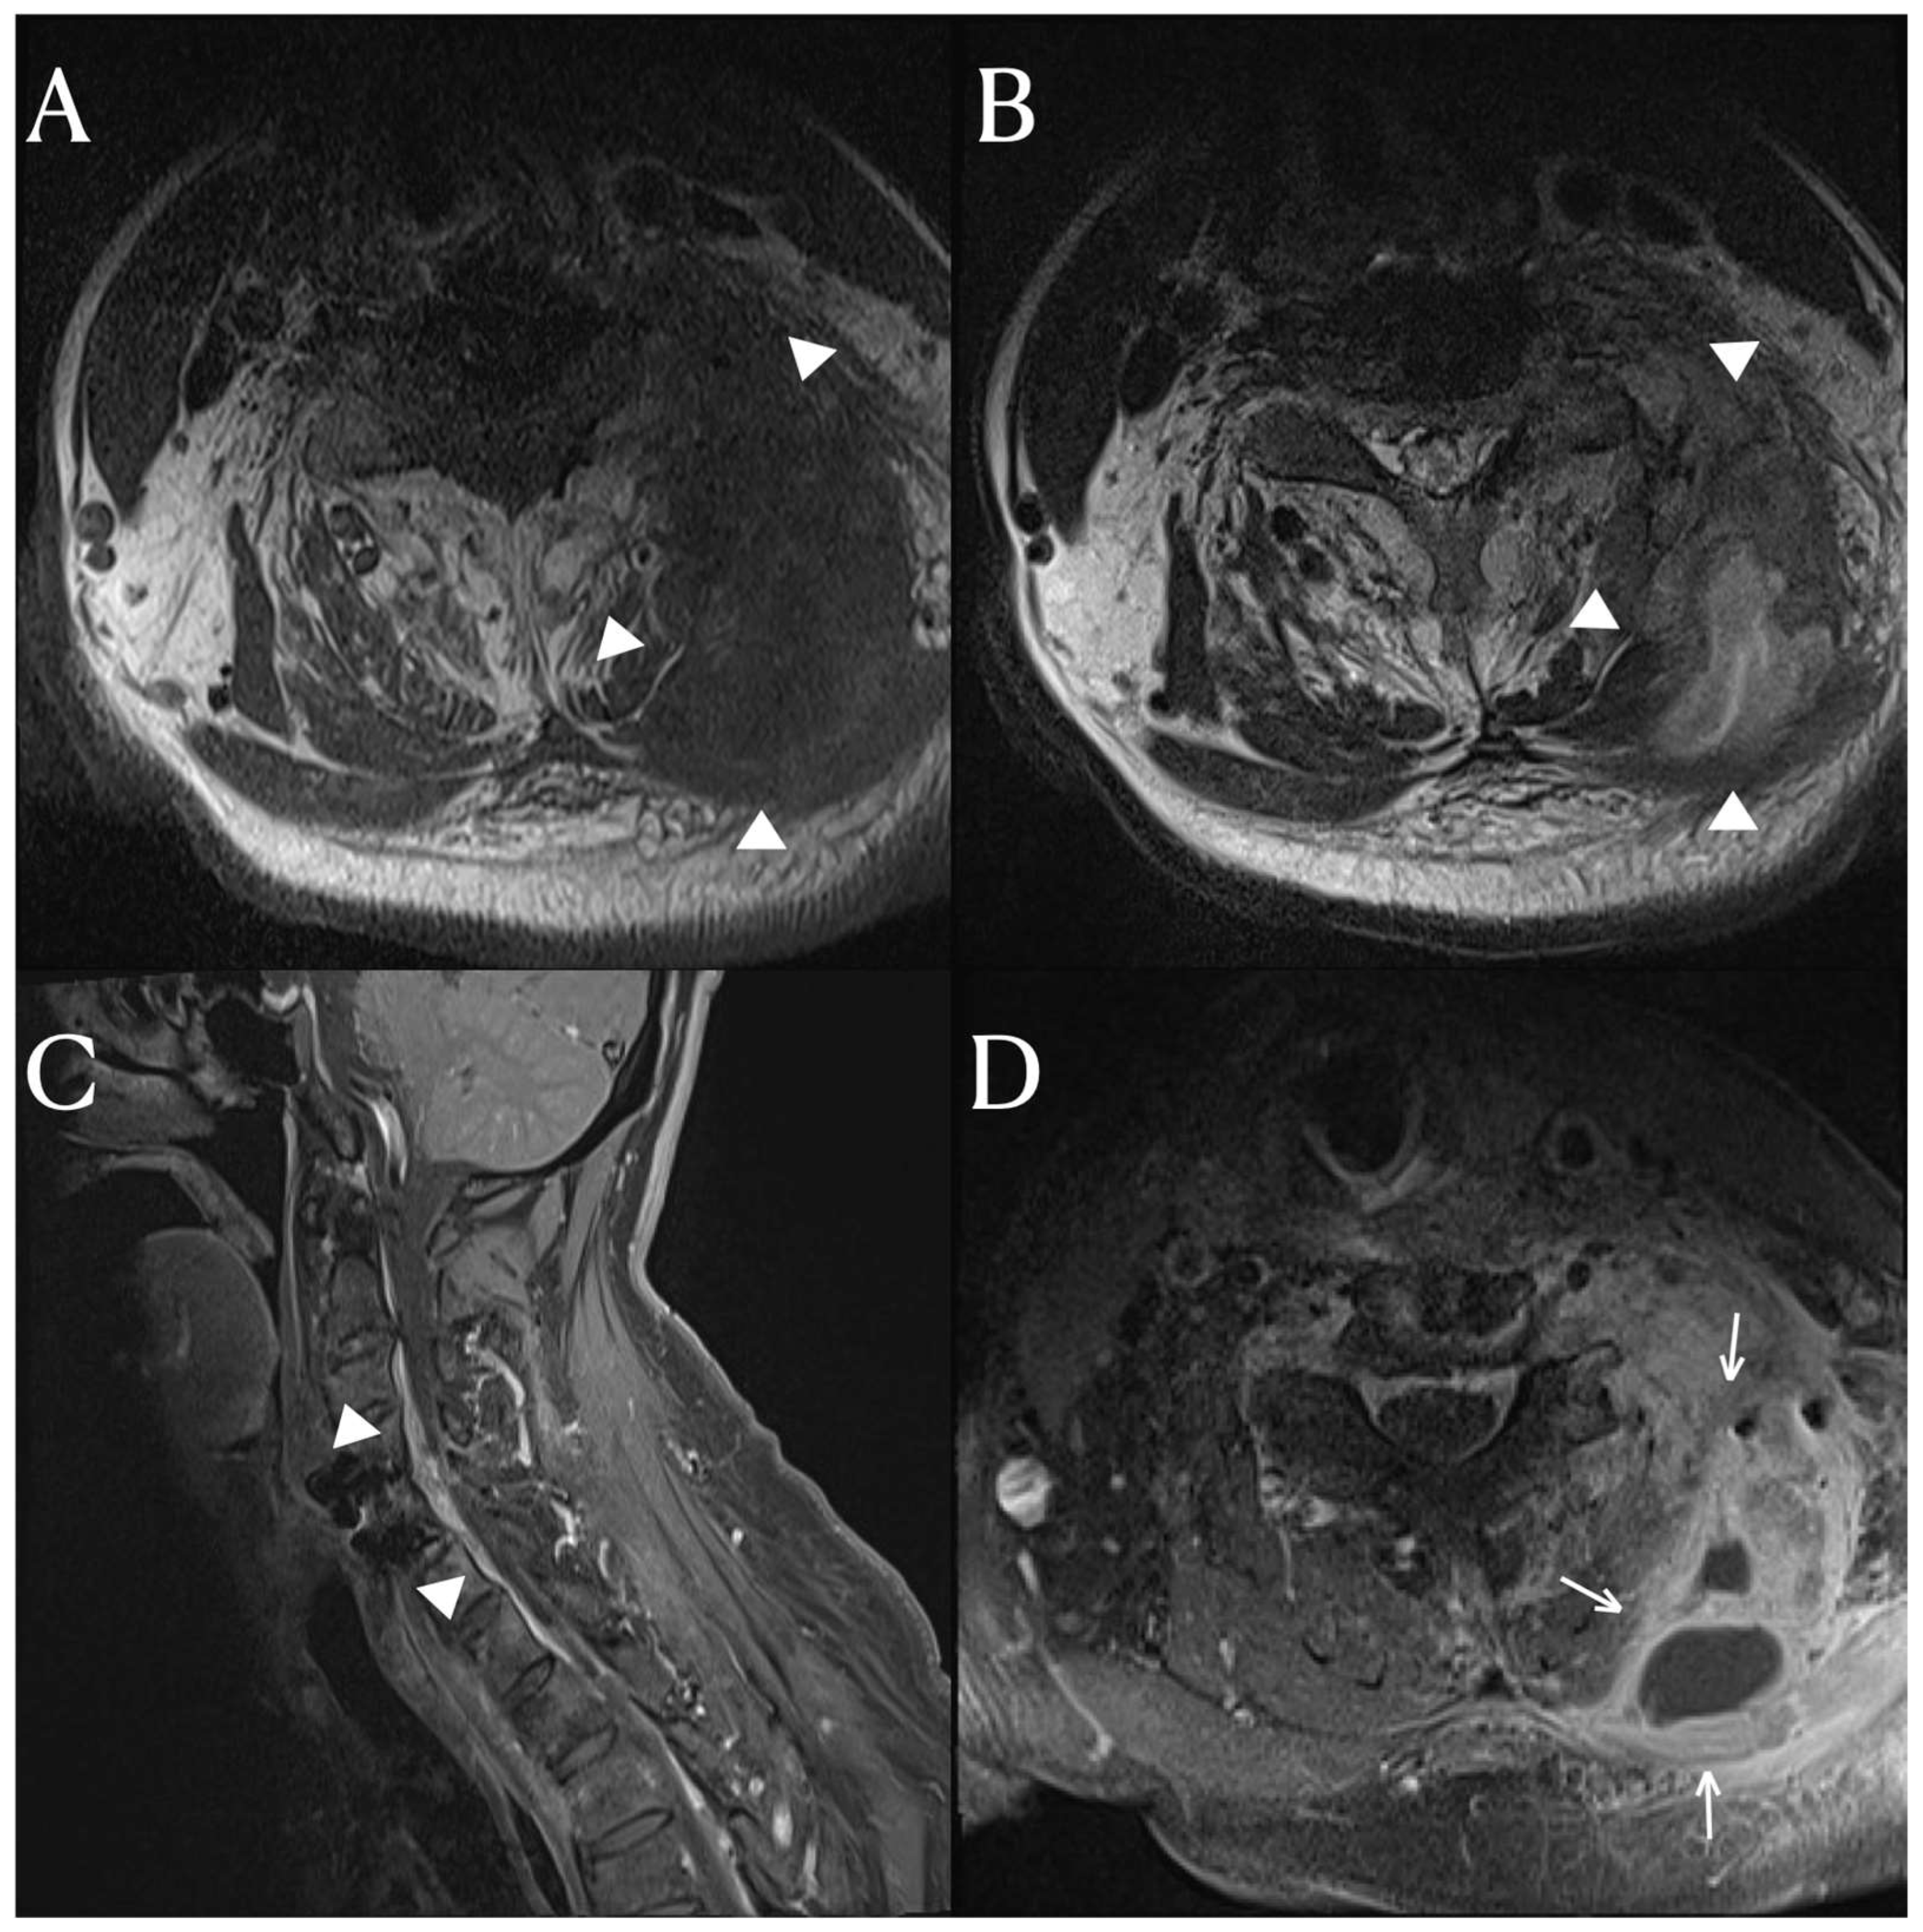

After three months of antibiotic treatment, the patient was discharged due to the improvement of the infection and abscess. However, the patient was readmitted a month later with symptoms of a systemic infection and the formation of an abscess on the posterolateral side once again. To manage the pus drainage, an incision and open drainage were performed. During the subsequent course of antibiotic treatment, food particles were observed in the previously excised drainage pathway. Furthermore, an endoscopic examination revealed an esophageal rupture with protruding hardware of the cervical fusion. (Figure 2) Considering the medical risks of operative repair, a percutaneous endoscopic gastrostomy was performed, and there were no further recurrences of infection after that.

Figure 1. The cervical spinal MRI images, T1 (A) and T2 (B) weighted axial scans revealed an inter-intramuscular abscess (arrowhead) involving the left scalene, multifidus, semispinalis cervicis, and semispinalis capitis muscles, as well as the levator scapulae. The T1-weighted enhanced axial scan (D) displayed a rim-enhanced fluid collection (arrow) indicative of an abscess. The T1-weighted sagittal scan (C) demonstrated an epidural abscess (arrowhead) extending from the C3 to C6 levels.

Figure 2. There was a drainage pathway (black arrow) on the posterolateral side of the left neck for the cervical abscess. (A) On the endoscopic examination, a metallic device (white arrow) was observed protruding into the esophagus (B).